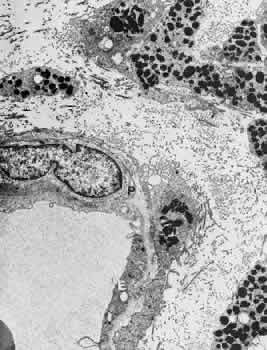

In the retrolaminar zone, the contribution of the choroidal vessels is less. The peripheral aspects of the postlaminar optic nerve are supplied by the pial vessels, whereas the central portion is fed by the axial vessels off the CRA. The afferent channels derived from the short PCAs that cross the border tissue of Elschnig at the level of the choroid have a diameter ranging from 10 to 17 μm.36,37 They quickly branch into a tridimensional vascular network with a polygonal capillary bed. The capillary bed is nonfenestrated, with tight junctions. Numerous pericytes surround the endothelial cells. The capillary mesh measures from30 × 50 μm to 50 × 80 μm, and there are multiple arterial feeding points into the meshwork. The density of the meshwork seems equal in all disc quadrants. Although the capillary bed of the optic nerve head is derived mostly from posterior ciliary vessels, it more closely resembles the retinal capillary bed morphologically than the choriocapillaris. The major efferent vessel for this area of the optic nerve is the CRV. Some of the prelaminar drainage may be through the choroid as well. Direct communications between the CRV and choroidal veins may exist as a result of CRV obstruction or as anatomical variants, which would make the eventual drainage system the vortex veins. The surface capillaries of the optic disc are derived from the retinal vessels.35,37 They anastomose with capillaries of the retina. The prelaminar, choroidal-derived vessels may contribute somewhat to the surface capillary supply. The postcapillary venules that drain the RPC system cross over the disc margin to join with larger venules of the CRV system. It may be these terminal endings of the RPC that bleed with papilledema and other causes of disc swelling. The blood flow to the optic nerve head appears to be under local autoregulatory control.38–40 This flow pattern is similar to the retinal circulation. The site of the autoregulation is not clear; however, both endothelial cells and pericytes probably have a role. The clinical appearance of optic nerve blood vessels in various pathologic conditions has been the focus of intense interest. Alterations in optic nerve blood vessels associated with advancing glaucoma have been an area of particular study in light of the theories concerning a vascular origin for the disease. Quigley and colleagues41 noted that the density of optic nerve head capillaries did not appear to change with worsening glaucoma and that eventual loss of capillaries was in proportion to the accompanying loss of neural tissue. Jonas and associates42 showed that the diameter of parapapillary retinal blood vessels was smaller in eyes with advanced glaucoma than in eyes without glaucomatous damage. This finding appears to represent an autoregulatory response of the retinal and optic disc vasculature to the local loss of retinal ganglion cells and nerve fiber layer. This study confirms an earlier report showing a significant decrease of RBF to the retina in eyes that had undergone inner retinal degeneration.43 CHOROID The choroid is by far the most vascular portion of the eye and by weight is one of the most vascular tissues in the body.44 More than 80% of all ocular blood flow goes to the choroid. The choroidal circulation is responsible for the nourishment of the photoreceptor/retinal pigment epithelium (RPE) complex. Despite these facts, the choroidal circulation has received relatively little attention for two reasons. First, it is difficult to visualize the choroidal vessels directly, and second, there are relatively few pathologic conditions that have unequivocally been associated with a primary deficiency in choroidal circulation. Choroidal blood flow can be assessed in a qualitative manner with fluorescein angiography. The rapidity of choroidal filling, the normal permeability of the choriocapillaris, and the normal blockage of fluorescence as a result of the RPE impede the identification of choroidal perfusion defects. When present, the clinical significance of choroidal perfusion defects on fluorescein angiography is not always clear, either. Newer methods used to study choroidal perfusion more quantitatively include indocyanine green angiography and color Doppler ultrasonography.45,46 Indocyanine green angiography in particular has made the choroid more accessible to clinical evaluation and interpreting the role of the choroid in various disease entities. Along with its paramount task of providing nutrition to the outer retina and RPE, the choroidal circulation also has other roles. It serves as a heat sink, removing the large amount of heat that develops as a result of the metabolic processes initiated when photons strike the photopigments and RPE.47 In addition, the choroid itself probably serves as a mechanical cushion for the internal structures of the eye. The overall structure of the choroidal circulation is segmental.47–52 This segmental distribution of blood begins at the level of the posterior ciliary branches and is mirrored in the vortex vein drainage system. Because of the segmental distribution, the large and medium-sized choroidal arteries act as end arteries. Unlike most other tissues, in the choroid the large vessels do not run parallel to each other. The segmental distribution of blood flow to the choriocapillaris is reflected in certain disease states, such as malignant hypertension. Each terminal choroidal artery supplies an independent lobule of choroidal capillaries (Figs. 11 and 12). Examination of the lobular structure reveals that feeding arterioles are usually found in the lobule center with draining venules located at the lobular periphery, but reversals of this pattern are frequently seen. There is little or no functional communication between adjacent capillary lobules.53–56 The vasculature of the choroid appears to be under direct adrenergic innervation.13,57 It is hypothesized that the parasympathetic innervation is through the seventh cranial nerve by way of the pterygopalatine ganglion.58 Arteries and Arterioles Within the choroid, the arteries and arterioles lie in stratified layers, with the larger vessels located in the outermost layer. The innermost layer of choroidal vessels is a single layer of capillaries. The arteries of the choroid measure between 20 and 90 μm in diameter.59 The larger vessels contain an endothelium and basement membrane, an internal elastic membrane, and a single continuous layer of smooth muscle cells. The muscle cells contain abundant myofilaments, and pinocytotic vesicles are arranged along the inner surface of the plasma membrane. The adventitia is composed of bundles of collagen fibers, scattered elastic fibers, and occasional fibroblasts. In the smaller vessels (arterioles), the internal elastic membrane disappears, and the muscle layer becomes discontinuous and more circumferentially arranged. The collagen present in the adventitia also becomes considerably diminished. Veins and Venules The choroidal veins that directly feed the vortex veins have a diameter less than 150 μm.59 The veins with a diameter between 50 and 150 μm have an endothelium and basement membrane with one or two layers of smooth muscle and a relatively thick collagenous adventitia. In the venules (smaller than 40 μm), the intima is the same, but the media contains a discontinuous layer of longitudinally arranged pericytes. Choriocapillaris The choriocapillaris is the unique capillary system of the choroid. The vessels of the choriocapillaris are unusual because of their large diameters. The lumina are typically larger than 8 μm. Lumina of this size allow passage of multiple red blood cells at any moment in time. The choriocapillaris is arranged in a specific lobular pattern to ensure maximum exposure of the overlying outer retina/RPE complex. Each lobule acts as an independent vascular system with its own afferent and efferent vessels.60 Within the posterior pole region, there are more venules than arterioles, probably to allow rapid flow. Other local variations exist. The lobules at the posterior pole are 200 to 400 μm in diameter and gradually enlarge to 1,500 μm in the periphery and somewhat lose their lobular pattern (Fig. 13).54,61 The vessel walls themselves consist of fenestrated endothelium surrounded by a basement membrane and a sparsely arranged layer of pericytes. The portion of the endothelial cell containing the nucleus also contains most of the cell's cytoplasm and organelles. The remainder of the cytoplasm is extremely attenuated, and these regions contain the fenestrae. These fenestrae are approximately 700 to 800 nm in diameter and are covered by a diaphragm. The attenuated areas are most typically found facing the RPE and contain very few pinocytotic vesicles. The region of the cell facing the suprachoroidal space usually contains more cytoplasm, fewer fenestrae, and the nucleus (Fig. 14). Few pericytic processes are seen in cross sections of these vessels on the side of the vessel facing the pigmented epithelium (Fig. 15). However, these processes are more numerous on the surface of the vessel facing the sclera. Because of the fenestrae, the choriocapillaris actively leaks fluorescein molecules.